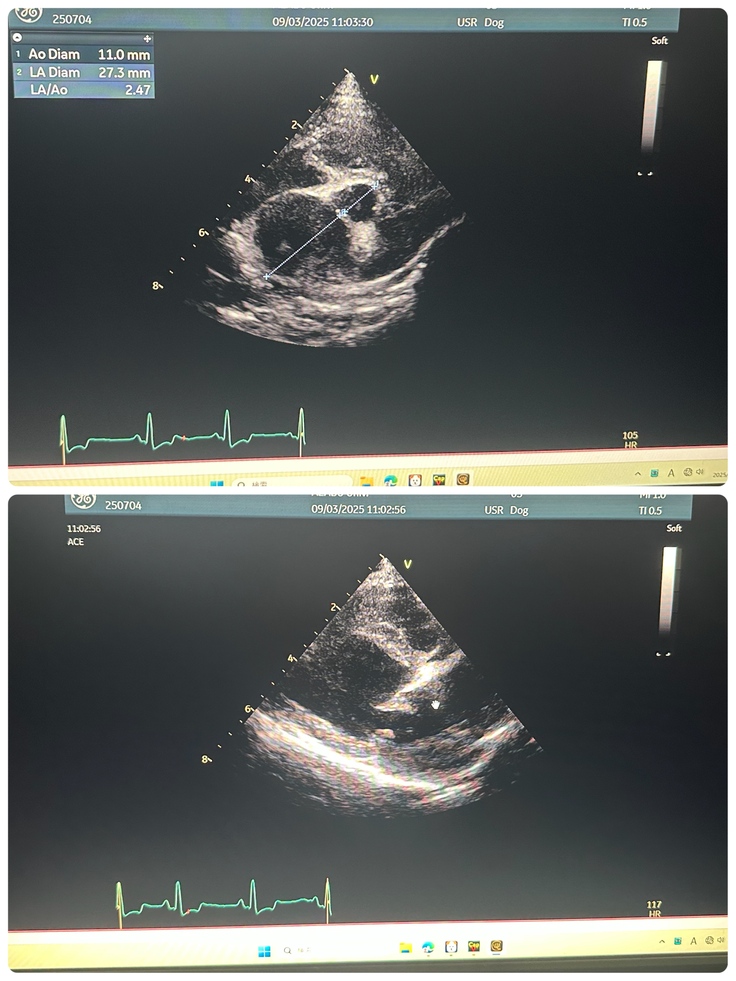

手術前検査

かかりつけ医から紹介していただいた大学病院にて手術することが可能なのか、いまの状態を検査してもらいました。

検査結果は手術適応。

9/3エコー

今現在腱索が全て切れた状態でフレイルが起きており、心臓内の血液が約50%ほど逆流している状態です。体内に回るはずの血液が肺にも逆流しておりなるべく早く手術をしないと肺の大きさも元に戻らない可能性もあるそうです。